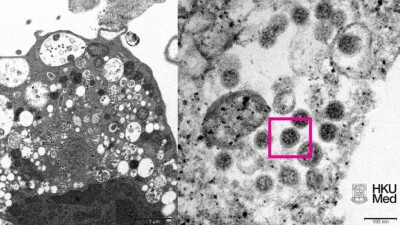

Микрочипы, рак, бесплодие. Что нужно знать о вакцинах от Covid-19